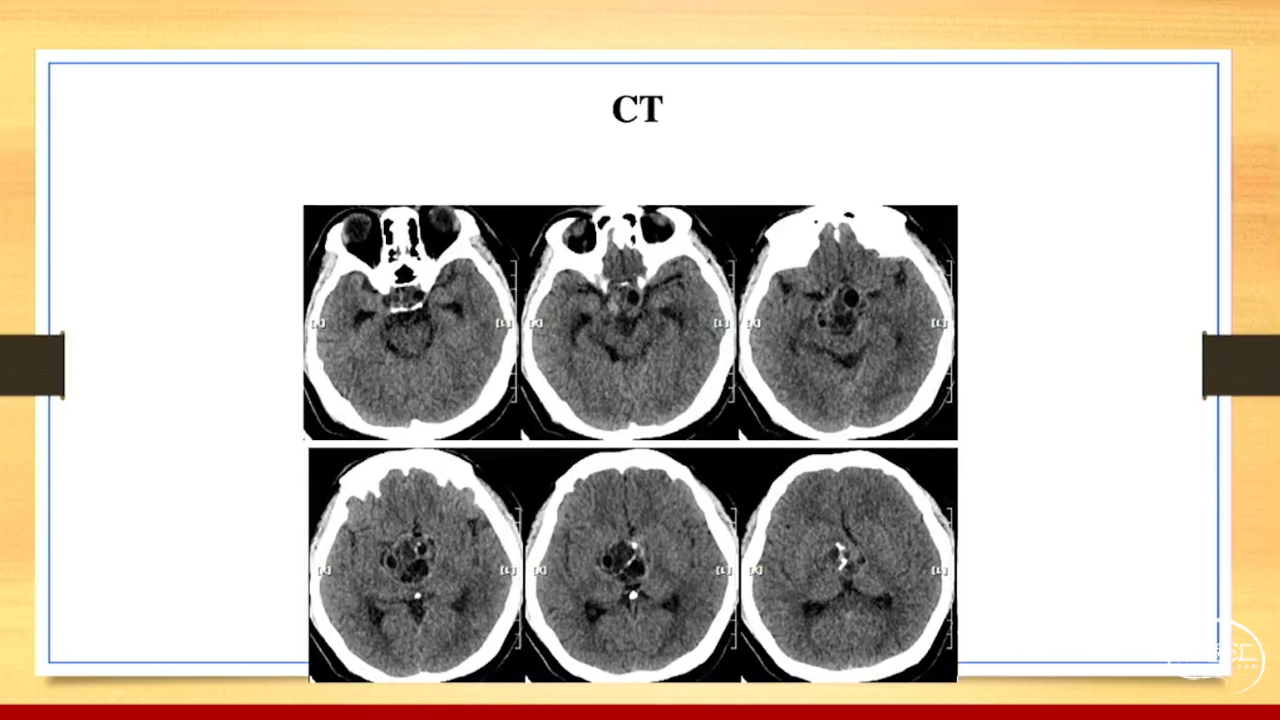

张荣教授:儿童颅内生殖细胞瘤的手术治疗

颅内生殖细胞肿瘤的治疗是手术、放疗、化疗、内分泌及其他多学科的整合治疗。及时、精准、合理的手术治疗是iGCT患者提高生存率、降低并发症、改善神经内分泌功能的关键。